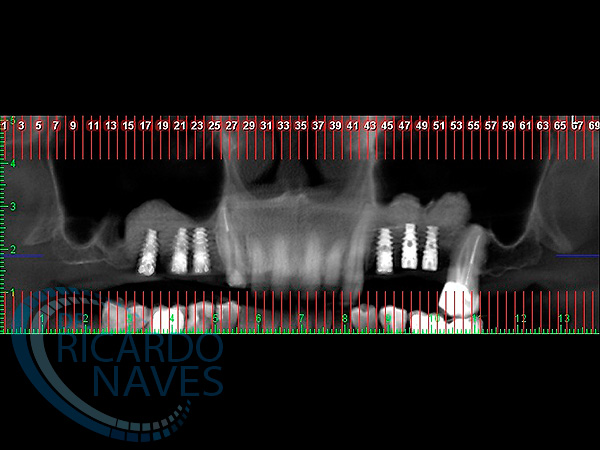

Elevación de seno maxilar con aloinjerto e instalación inmediata de implantes.Control a los 15 días post cirugía.VOLVER Comparte esta historia, elija su plataforma! FacebookXLinkedInPinterestCorreo electrónico